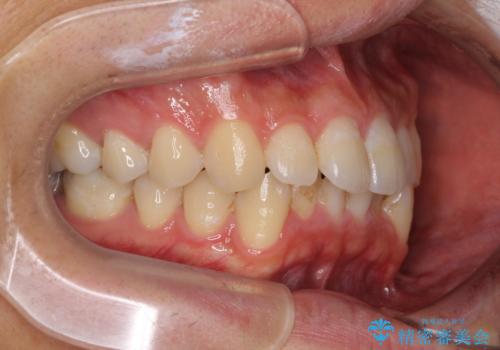

口が少し閉じにくい インビザラインによる非抜歯矯正

- 口元の突出感を治したいとのことで来院された患者様です。

上下顎ともにIPR(歯と歯の間を削る)と歯列全体の拡大によって口元が引っ込むように設計し、インビザラインにより治療を行うこととしました。

抜歯をして口元を下げなければならないほど出っ歯ではなかったため、少しずつ治療ゴールを変更しながら仕上げていきました。

気になっていた前歯の飛び出した印象は、最終的にはスッキリと引っ込み、大変満足していただきました。